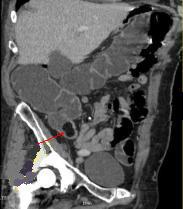

Lipome siegent portion ileo-

coecale . Image TDM en coupe sagitale ( fleche rouge

) |